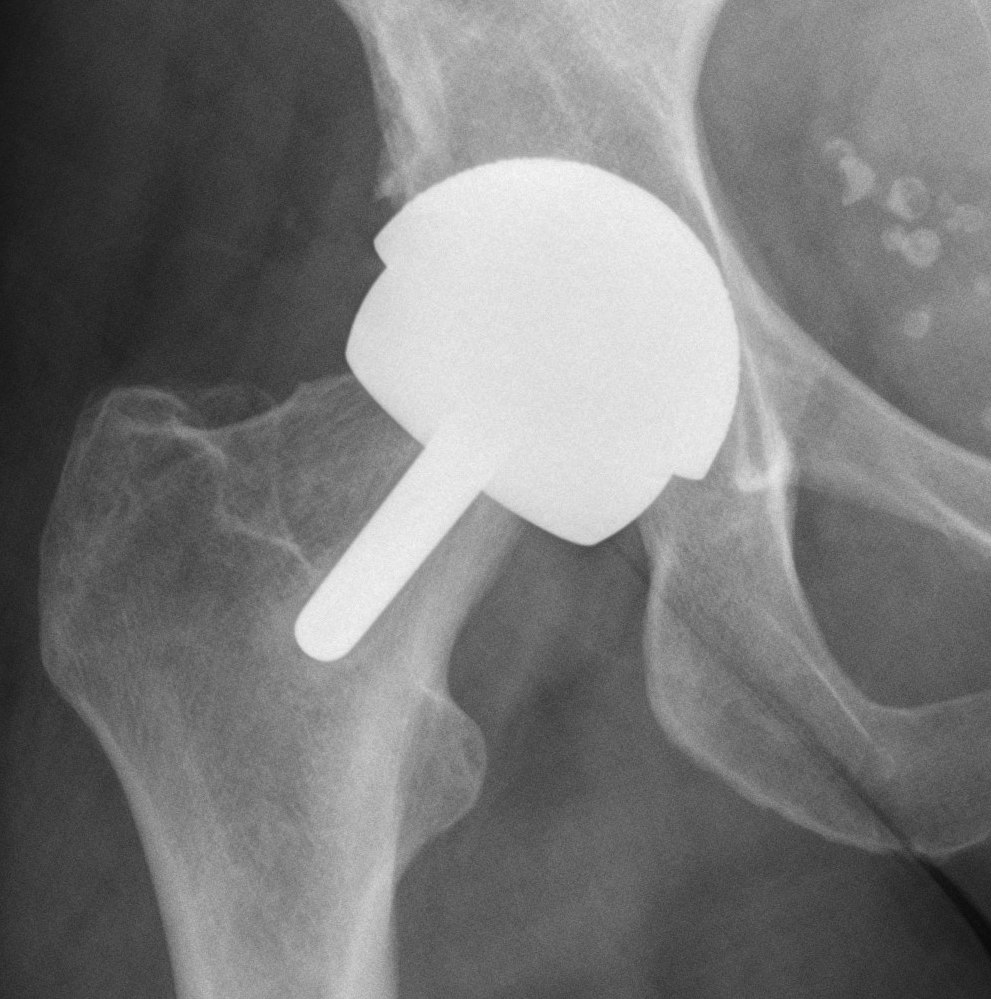

Birmingham hip resurfacing

Concept

Femur - removal of femoral head cartilage and resurfacing with metal

Acetabulum - standard technique

Bearing surface - metal on metal